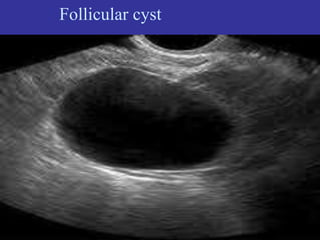

1- Follicular cyst :

The most common type, forms when the follicle grows larger

than normal and does not open to release the egg. Cysts can

contain blood (hemorrhagic cysts) .

Follicular cyst